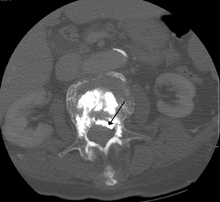

A CT image of cement used in kyphoplasty that has entered the spinal channel and is pressing on the spinal cord resulting in neurological symptoms

Some of the associated risks are from the leak of acrylic cement to outside of the vertebral body. Although severe complications are extremely rare, infection, bleeding, numbness, tingling, headache, and paralysis may ensue because of misplacement of the needle or cement. This particular risk is decreased by the use of X-ray or other radiological imaging to ensure proper placement of the cement.[19] In those who have fractures due to cancer, the risk of serious adverse events appears to be greater at 2%.[3]